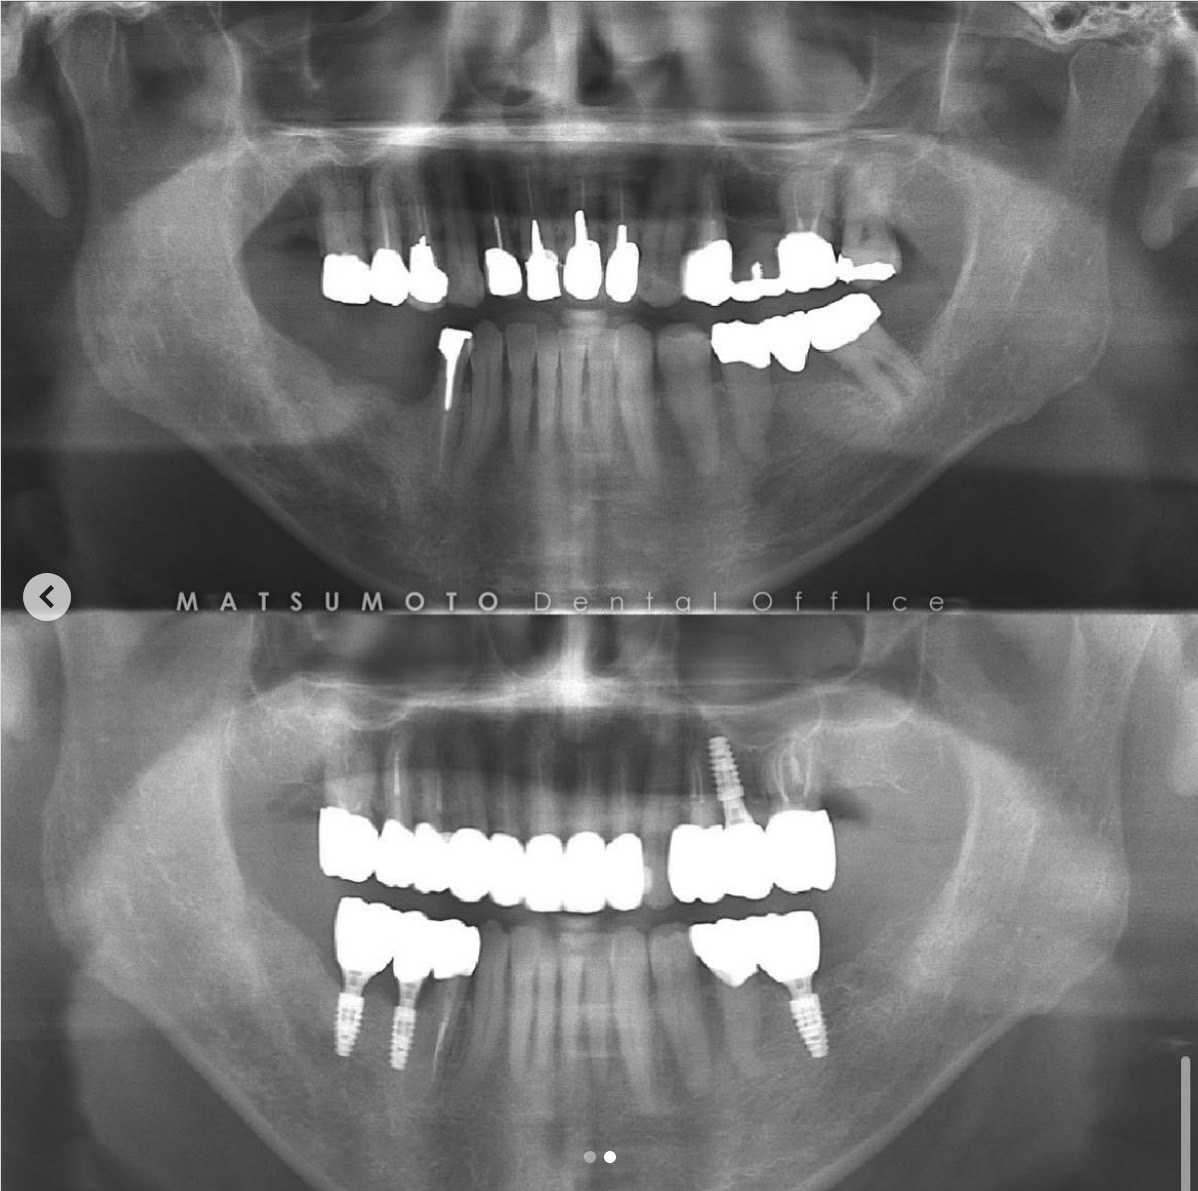

症例紹介28:オールオンシックス(All-on-6)インプラント治療《60代女性》

治療内容:現在他院で右上の根の治療をしているが、全体的に噛めないので治療を希望され来院。

術前の診査診断

術前写真

上顎:虫歯がひどく、保存不可能な状態である。

下顎:インプラントが入っているが、被せ物がなずれたまま放置になっている。

パノラマX線

上顎:根の病気と虫歯で保存不可のな状態。

下顎:インプラントが不適切な位置に入っており、撤去が必要な状態。

オールオンシックス(All-on-6)インプラント治療を終えて

最終補綴

上顎:両側サイナスリフト後のロケーターアバットメントによる金属床ブリッジ

下顎:All-on-6によるフルジルコニアブリッジ

治療のリスクと副作用

治療期間:約1年半

治療費:¥6,200,000(税込)

リスク:上顎のロケーターアバットは定期的に交換が必要です。また、上顎の人工歯が減ってきますので、定期的なメンテナンスが重要です。